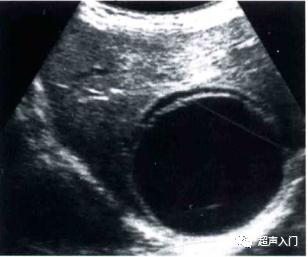

1、单囊型

表现为肝内出现单个圆形或类圆形无回声区,囊壁增厚完整,为中高回声,可呈双层,同时可出现细小的点状反射堆集于囊底,随体位改变而漂浮,形成“飘雪”征。

单囊型(CE1)

图源:人卫出版社教材及课件